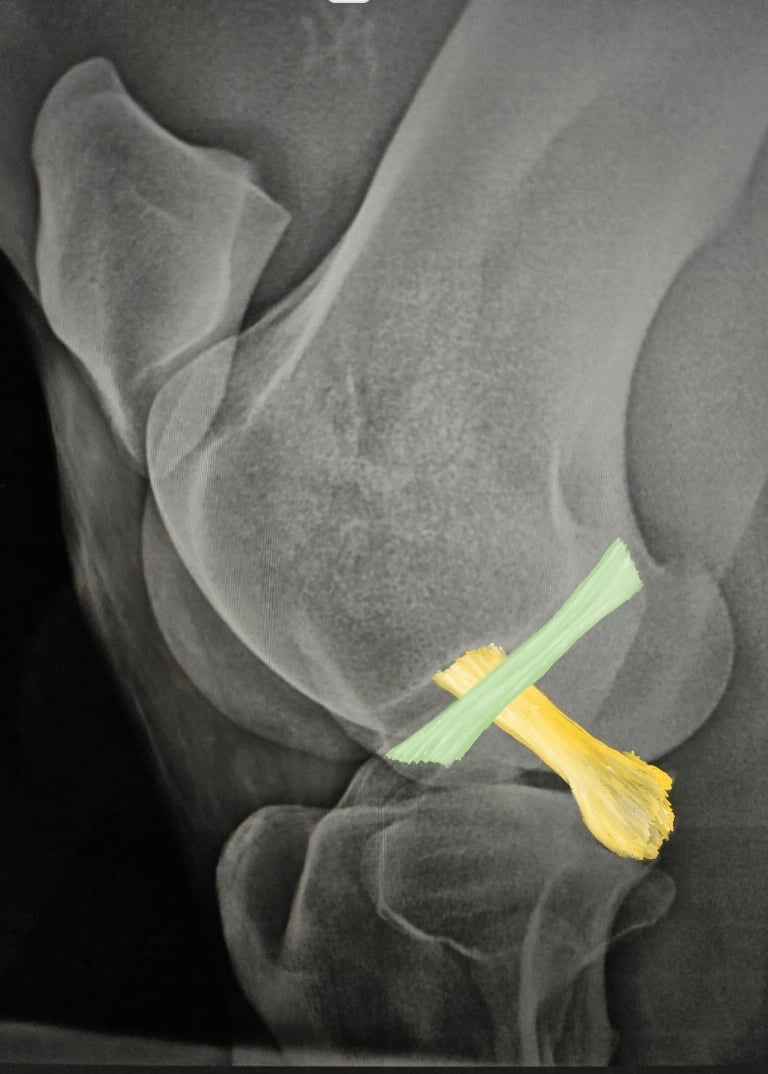

BLOQUEOS DIAGNOSTICOS